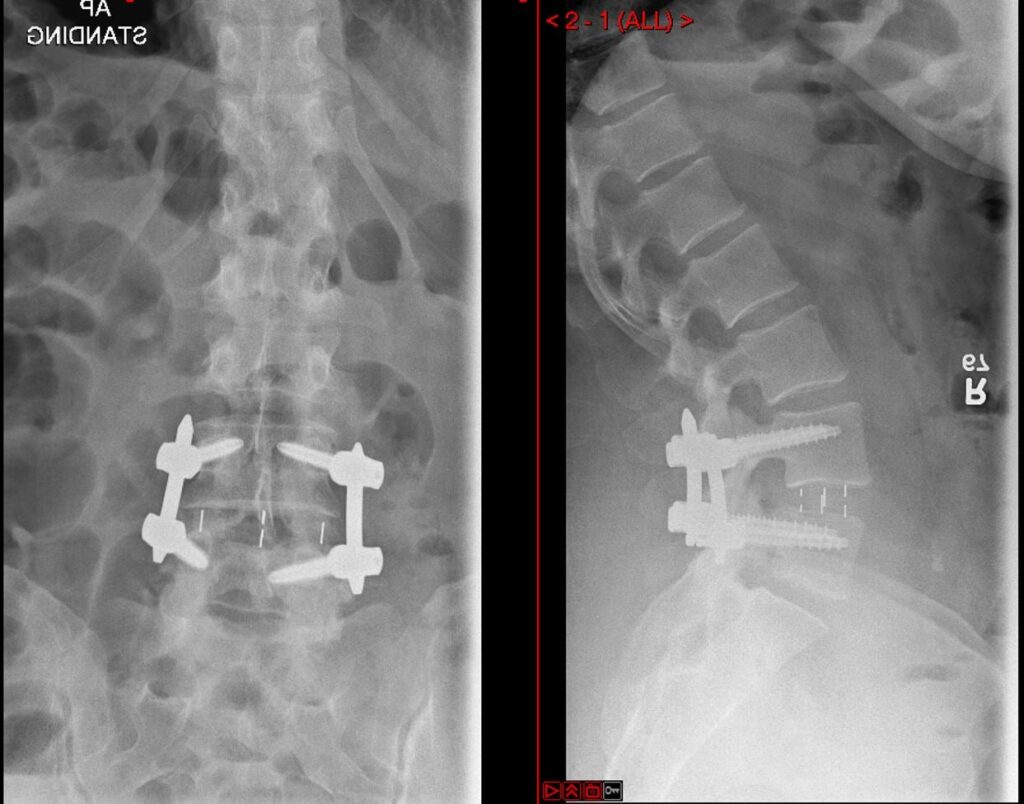

Oblique Lumbar Interbody Fusion